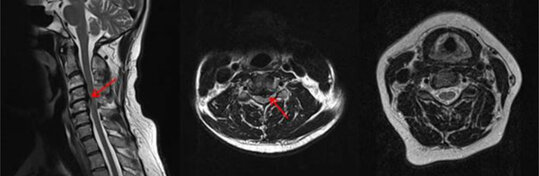

Spinalkanalstenose

Als Spinalkanalverengung bezeichnet man eine Verengung des Wirbelkanals aufgrund von Verschleißerscheinungen (Degenerationen). Sie tritt daher v.a. in höherem Alter auf. Durch die verschleißbedingten biomechanischen Veränderungen in den Segmenten der Wirbelsäule kommt es kompensatorisch z. B. zu Knochenanbauten und Verdickungen der Bandstrukturen. Diese Veränderungen führen in der Summe dann zu einer Verengung des Spinalkanals, in dem im Bereich der Hals- bis oberen Lendenwirbelsäule das Rückenmark und im Bereich ab der oberen Lendenwirbelsäule die Nervenwurzeln verlaufen. Werden diese Strukturen ebenfalls eingeengt, kommt es zu den typischen Symptomen. Beispielsweise klagen die Patienten bei Stenosen im Bereich der Halswirbelsäule über Gangunsicherheit, Schmerzen in Schulter und Armen, Feinmotorikstörungen der Hände, Sensibilitätsstörungen, Zunahme des Muskeltonus von Armen und Beinen. Im Endstadium kann sogar eine Querschnittssymptomatik auftreten.

Bei Stenosen im Bereich der Lendenwirbelsäule kann es zu belastungsabhängigen Schmerzen im Rücken und den Beinen kommen. Die Patienten können nur noch eine limitierte Strecke schmerzfrei gehen und müssen regelmäßige Pausen beim Gehen machen („Schaufensterkrankheit“). Ein Vornüberbeugen kann ebenfalls eine Besserung bringen. Unbehandelt kann es dann im Verlauf auch zu Lähmungen, Taubheitsgefühlen oder unkontrollierten Urin- und Stuhlabgang (Inkontinenz) kommen.

Konservative Therapiemethoden führen in der Regel nicht zum gewünschten Erfolg, sodass die Therapie der Wahl in der operativen Beseitigung dieser Engstellen besteht (z. B. durch Abfräsen von knöchernen Anbauten). Auch hier richtet sich die Operationsmethode nach der Lokalisation und Ausprägung der Stenose. Im Bereich der Halswirbelsäule wird die Operation z. B. in den meisten Fällen von vorne und im Bereich der Lendenwirbelsäule meistens von hinten durchgeführt. Sollte zusätzlich eine mechanische Instabilität vorliegen, ist ggf. zusätzlich eine Stabilisierung durch Schrauben, Platten etc. erforderlich (s. u.).